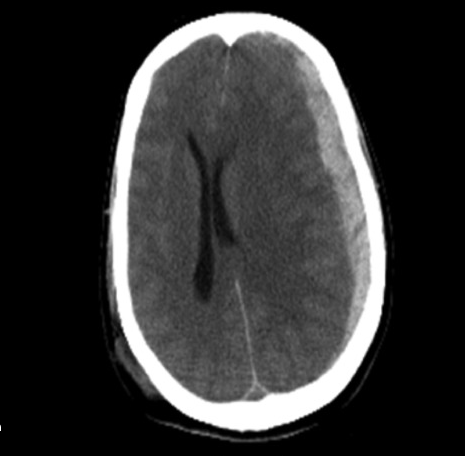

Que forma presenta el hematoma subdural en el estudio imagenologico ?

Hoz o Media Luna (Siguen el contorno del cerebro).